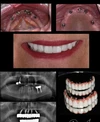

إغلاق المسافات بين الأسنان

الصور